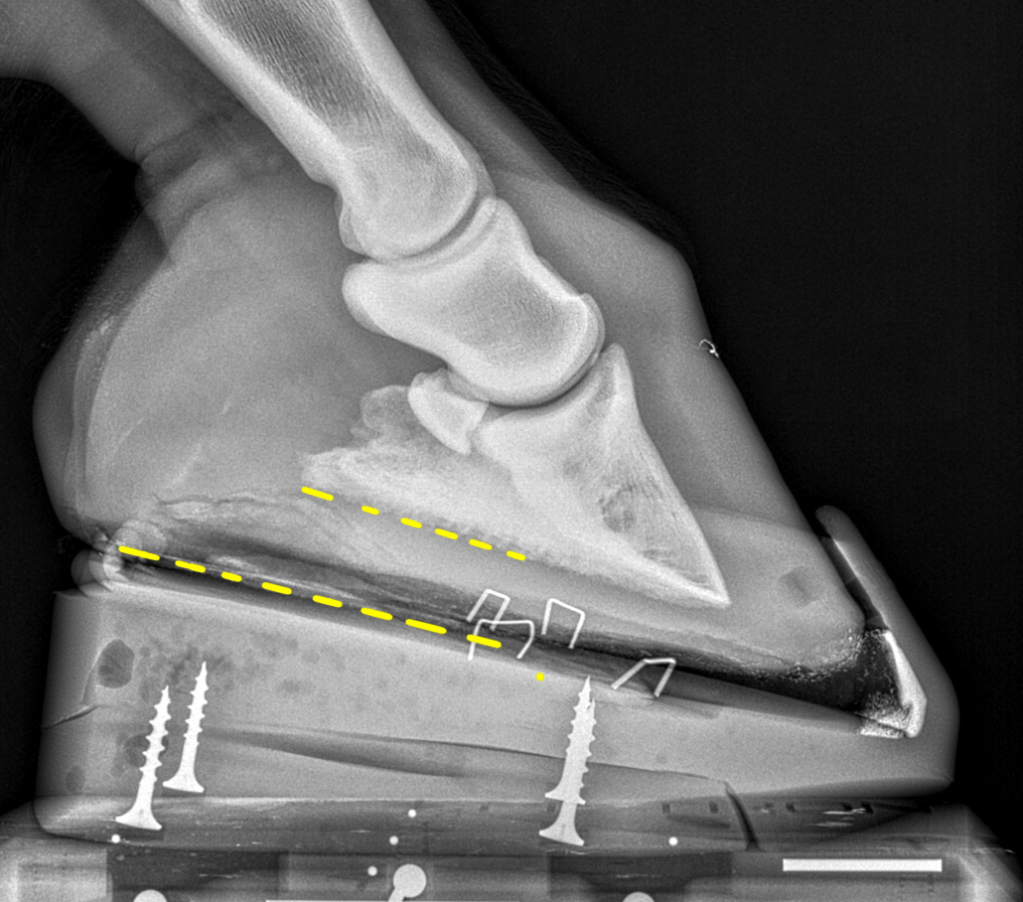

28 year old Haflinger gelding – overweight. He was placed in NANRIC Ultimates. Caloric intake was reduced and exercise was restricted.

The image at the far right includes the Ultimate which has been attached to the hoof with the bottom of the coffin bone parallel to the surface of the Ultimate. This is the most important thing because it shifts the horse’s weight to the heels, away from the toe. If we applied the Ultimate without getting the coffin bone parallel to the cuff then we would be increasing pressure at the toe making things worse.

2 months later the horse is sound, he has doubled his sole depth, and improved alignment. I gradually reduced the size of heel elevation and finally removed the Ultimates.